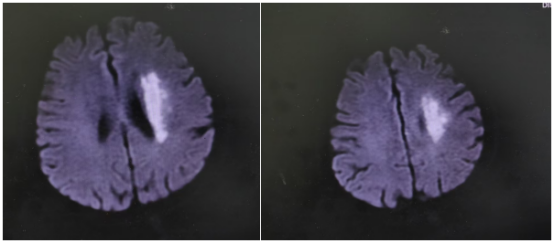

那天,71岁的符阿婆在家突发右侧肢体无力,说话也变得含糊不清。紧急送医后,检查结果令人揪心——左侧大脑中动脉M1段闭塞。

“当时情况非常紧急,”主管医生刘婷回忆道,“造影后发现符阿婆血管闭塞远端血流灌注严重不足,考虑是‘低灌注’导致核心梗死区周围的脑组织(缺血半暗带)也濒临坏死边缘。这意味着,虽然发病时间已较长,但仍有大量脑组织处在‘生死边缘’,若不立即干预,瘫痪将不可逆转。”

手术台上,一场与时间的赛跑再次开启。介入团队在DSA(数字减影血管造影)的精确引导下,将微导管、球囊等器械精准送达大脑深处闭塞的血管处。首先用球囊扩张,撑开狭窄闭塞的血管,随后成功植入一枚支架,牢牢“撑住”了病变血管,重建了血流。